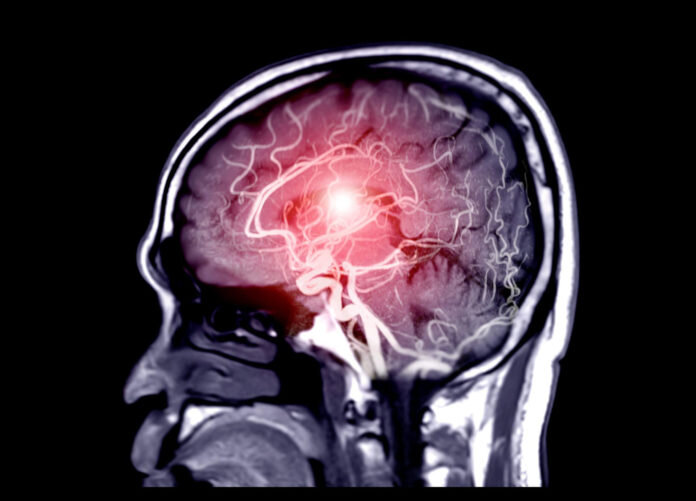

بر اساس گزارش ها، علائم این بیماری شامل مشکلات حافظه، اسپاسم عضلانی، کاهش شدید وزن، درد اندام و توهم است.

بر اساس آمارهای رسمی منتشر شده توسط یکی از مقامات بهداشتی نیوبرانزویک، تاکنون ۴۸ تن به این بیماری مبتلا شده و ۹ تن نیز جان خود را بر اثر ابتلا به آن از دست دادهاند.

این بیماری زنان و مردان را به طور مساوی تحت تأثیر قرار می دهد و اکثر بیماران مبتلا به آن در بازه سنی ۱۸ تا ۸۵ سال هستند.

یک مطالعه اپیدمیولوژیک توسط دپارتمان بهداشت نیوبرانزویک هرگونه ابتلا به این بیماری به دلیل غذا و تاثیرات محیطی را رد کرد.

به گزارش هوشمند نیوز به نقل از روزنامه گاردین، با این حال داده های مطالعه ای انجام شده توسط محققان کانادایی نشان داد افرادی که بر اثر ابتلا به این بیماری جان خود را از دست داده اند به دلیل تشخیص های اشتباه آن به عنوان بیماری های دیگری از جمله آلزایمر یا سرطان بوده است.